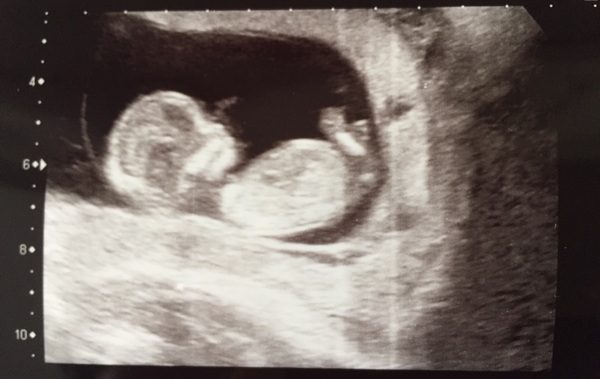

Successful scan today, very wriggly little bean. Brought my due date forward to the 17th May... so if I'm 13 weeks does that mean I stop feeling rubbish from today?!Hmm

NT measurement was 1.8 and they said I'd get a phone call by this time next week if there was anything to be worried about from the blood test. Hoping that since I'm a non smoker and a healthy weight all should be OK.

I thought I'd be all weepy in the scan but I just lay there in total awe... still not sure I really believe this is happening Smile

My scan went ok. The measurements were 2ish but they said it was within range and await phonecall if bloods come back differently.

There is two little wrigglers in there so it took ages! My poor bladder.